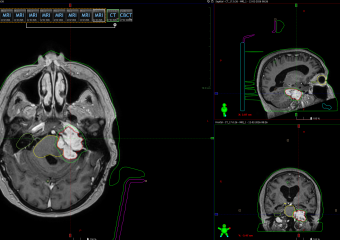

Varian TrueBeam позволяет проводить специальную высокоточную методику облучения высокими дозами за одну фракцию. Стереотакс основан на объемном планировании и высоко востребован в облучении как злокачественных, так и доброкачественных опухолей головного мозга.

До процедуры производится подбор фиксирующих устройств, чтобы обеспечить неподвижность пациента во время лучевой терапии. Затем проводятся топометрические исследования и оконтуривание опухолевого очага. Планирование осуществляется на станциях Monaco, что позволяет оптимально распределить подводимую к опухоли дозу.